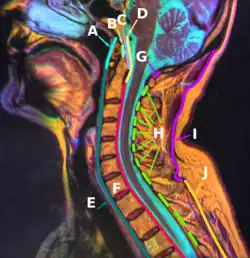

Membrana tectoria, transverse, and alar ligaments. ("Transverse ligament" and "vertical portion" visible intersecting at center.) | |

The cruciate ligament of the atlas (cruciform ligament) is a cross-shaped (thus the name) ligament in the neck forming part of the atlanto-axial joint. It consists of the transverse ligament of atlas, a superior longitudinal band, and an inferior longitudinal band.

The cruciate ligament of the atlas consists of the transverse ligament of the atlas, a superior longitudinal band, and an inferior longitudinal band.[1][2] The superior longitudinal band connects the transverse ligament to the anterior side of the foramen magnum (near the basilar part) in the occipital bone of the skull. The inferior longitudinal band connects the transverse ligament to the body of the axis bone (C2).[1]

The cruciate ligament of the atlas prevents abnormal movements of the atlanto-axial joint.[1] The longitudinal bands prevent hyperflexion and hyperextension of the occipital bone, and hold the transverse ligament of the atlas in a normal position.[1]